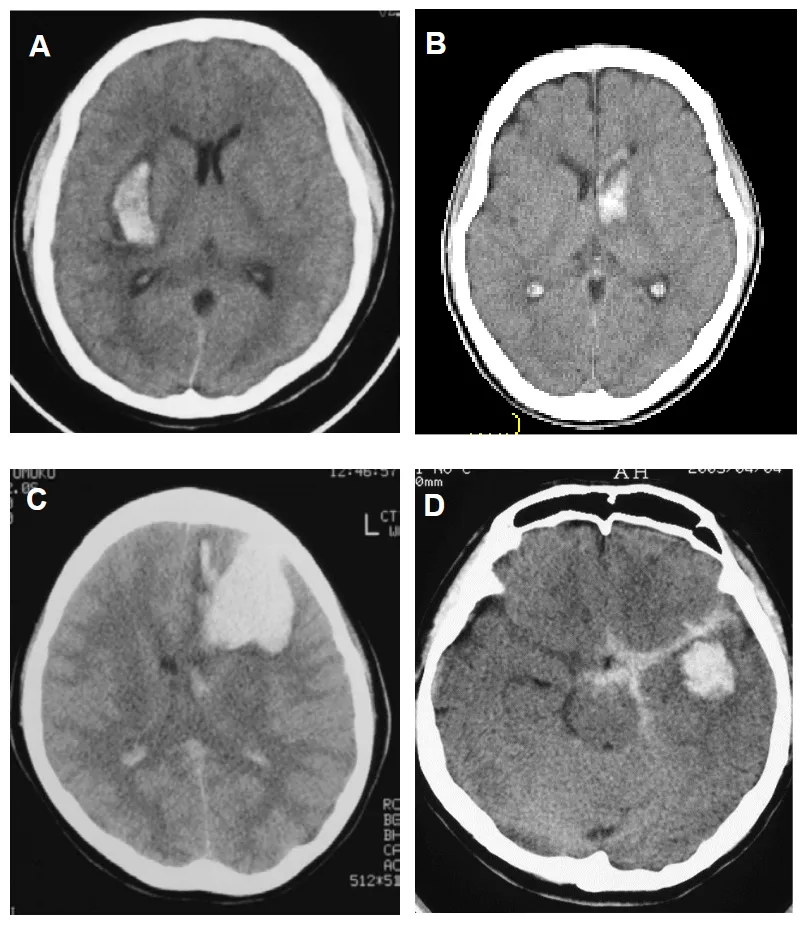

前部出血的代表性 CT 图像

A:壳核出血 B:尾状核头出血 C:额叶出血 D:颞叶前半部分出血

A:侧脑室前部室管膜下区出血;B:脑池前半段蛛网膜下腔出血;C:起源不明、弥漫分布的原发性脑室内出血